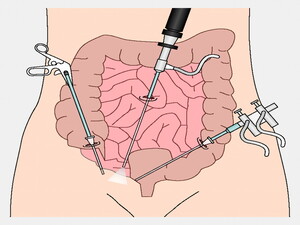

His special interests are in the field of Laparoscopic Hernia Surgery, Laparoscopic Upper G.I Surgery, Laparoscopy in Gastrointestinal Cancers and Bariatric Surgery. He is also actively involved in publications in peer – reviewed journals.